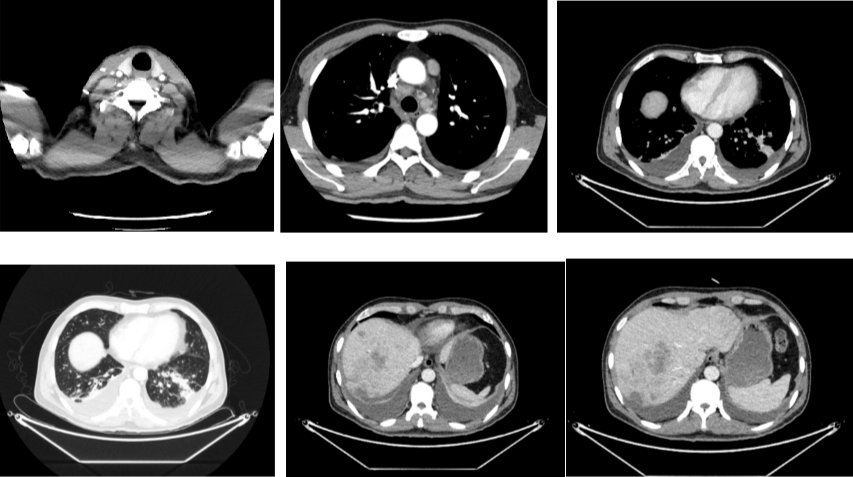

2018-11-14 CT(8周期化疗后):PD?

△基线水平

△治疗后

2018-11-19 PET/CT

胃壁代谢稍增高但未见明确的肿物,肝内低代谢结节考虑转移瘤治疗后活性减低,纵膈及右肺门两个淋巴结代谢增高,考虑转移瘤活性尚存、左侧颞骨局部骨质破坏并代谢增高,考虑转移瘤。

经科内讨论,建议患者继续原方案SOX+赫赛汀化疗,左侧颞顶交界区骨质破坏局部射波刀治疗。